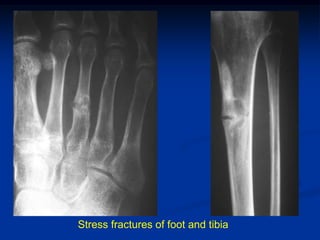

Case #6

Non Familial Hypophosphatemic Osteomalacia

Stress fractures of foot and tibia